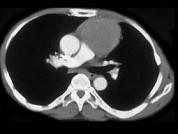

男,57岁,胸部隐痛2月余,请结合影像学检查,选出最可能的诊断 ( )A.纵隔畸胎瘤B.淋巴瘤C.支气管囊肿D.胸内甲状腺肿E.胸腺瘤

问题 男,57岁,胸部隐痛2月余,请结合影像学检查,选出最可能的诊断 ( )

选项 A.纵隔畸胎瘤 B.淋巴瘤 C.支气管囊肿 D.胸内甲状腺肿 E.胸腺瘤

答案 E